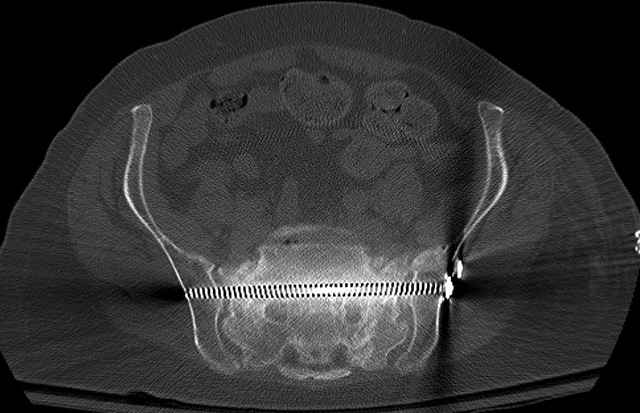

Pelvic CT Scan - 3 Months After Fall

Sacral Injuries

Ramus Fractures